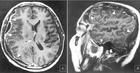

當疑顱內有局限性膿腫,硬腦膜下積液、腦積水可作腦CT檢查。